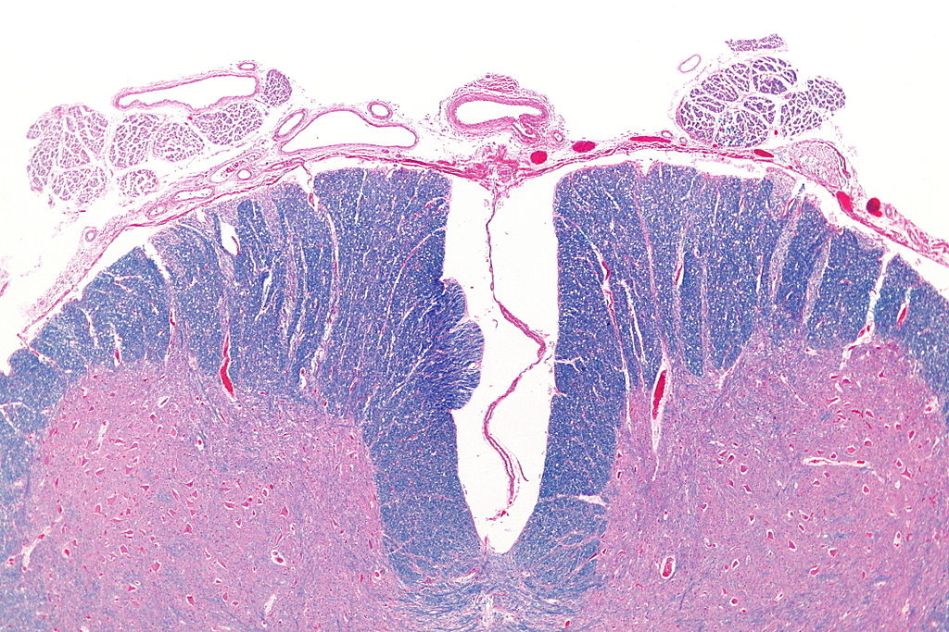

Spinal cord cross section with the anterior artery showing (top)